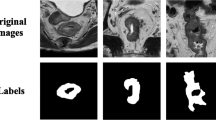

Accurate segmentation of rectal tumors is the most crucial task in determining the stage of rectal cancer and developing suitable therapies. However, complex image backgrounds, irregular edge, and poor contrast hinder the related research. This study presents an attention-based multi-modal fusion module to effectively integrate complementary information from different MRI images and suppress redundancy. In addition, a deep learning–based segmentation model (AF-UNet) is designed to achieve accurate segmentation of rectal tumors. This model takes multi-parametric MRI images as input and effectively integrates the features from different multi-parametric MRI images by embedding the attention fusion module. Finally, three types of MRI images (T2, ADC, DWI) of 250 patients with rectal cancer were collected, with the tumor regions delineated by two oncologists. The experimental results show that the proposed method is superior to the most advanced image segmentation method with a Dice coefficient of \(0.821\pm 0.065\), which is also better than other multi-modal fusion methods.

Framework of the AF-UNet. This model takes multi-modal MRI images as input, and integrates complementary information using attention mechanism and suppresses redundancy.